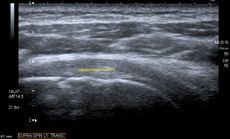

الموجات فوق الصوتية